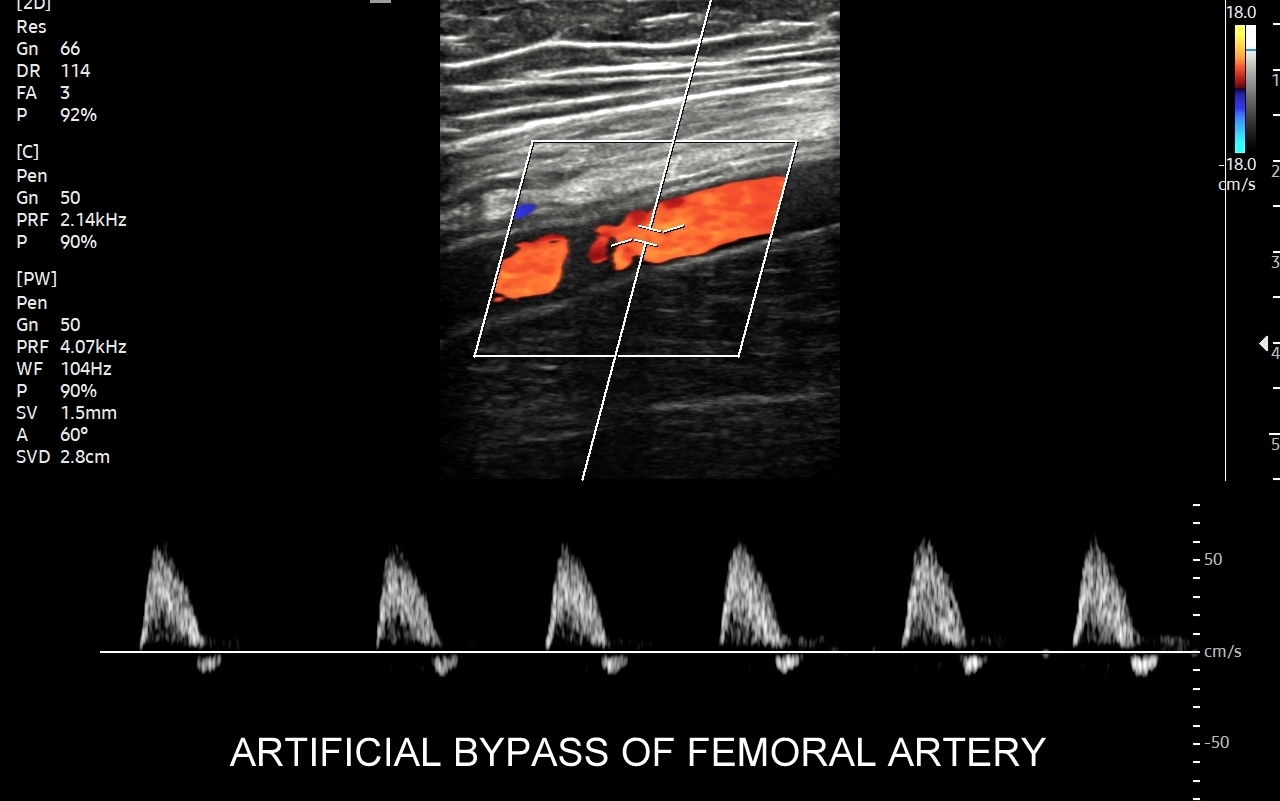

Badanie USG Doppler tętnic, klasyczne badanie angiograficzne oraz badanie angio-TK to podstawowe i uzupełniające się metody diagnostyczne naczyń. Badanie dopplerowskie w przeciwieństwie do dwóch pozostałych jest metodą oceny funkcjonalnej a nie tylko wizualnej, tzn. oprócz stopnia zwężenia tętnicy ocenia również zaburzenia przepływu w oraz za zwężeniem, a także zaburzenia ukrwienia dystalnego tkanek.

Badanie USG Doppler tętnic kończyn dolnych wykonywane jest najczęściej w ramach diagnostyki miażdżycy zarostowej tętnic kończyn i jej objawów w postaci chromania przestankowego, czyli bolesności łydek, rzadziej ud i pośladków, pojawiających się w trakcie wysiłku fizycznego. Inne wskazania do USG tętnic kończyn dolnych obejmują uczucie chłodnych stóp, marznięcie nóg, diagnostykę zespołu zespół  Raynauda, czy choroby Buergera. W stanach nagłych badanie wykonuje się w przypadku ostrego niedokrwienia np. na tle obwodowej zatorowości tętniczej. Rzadsze patologie, które pojawiają się w obrębie tętnic kończyn dolnych to tętniaki prawdziwe, tętniaki rzekome (pseudotętniaki) i rozwarstwienia. Tętniaki rzekome są zwykle efektem powikłań jatrogennych nakłuć, a rozwarstwienia wynikiem urazów tętnicy, np. podczas uprawiania sportu.

Podczas wykonywania USG Doppler kończyn dolnych bada się osie tętnicze obu kończyn, które obejmują takie tętnice jak tętnica udowa wspólna, powierzchowna, głęboka, podkolanowa, tętnica piszczelowa przednia, tylna i tętnica strzałkowa. Ocenia się również ewentualne zwężenia oraz tzw. krążenie oboczne; poszukuje się cech zatorowości, zapalenia, rozwarstwienia i cech tętniaków.